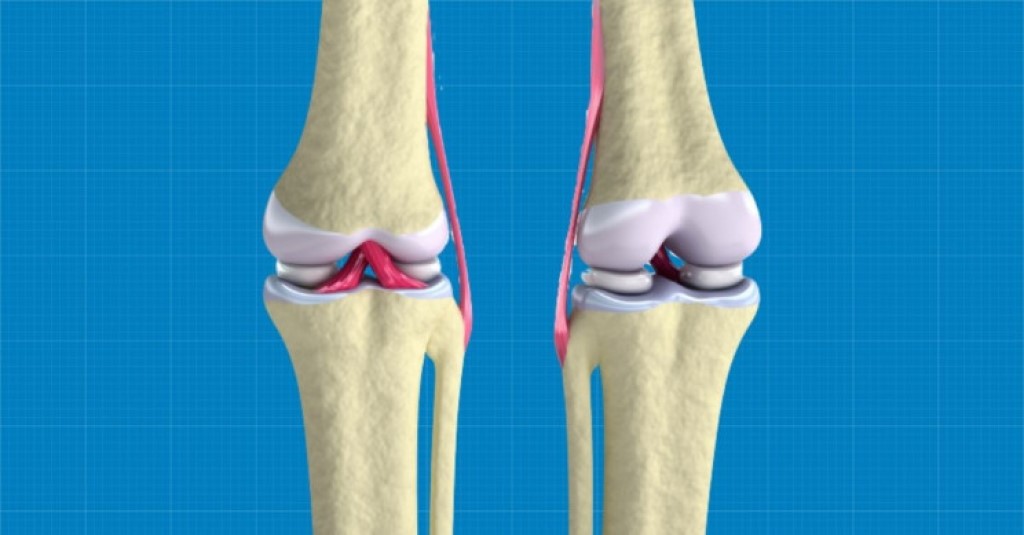

Redwire 3D Bioprints a Human Knee Meniscus in Space

Bioprinting Cartilage Tissue To Help Knees Function Again

The Wake Forest Institute has bioprinted regenerative knee cartilage tissue to replace damaged knee cartilage.